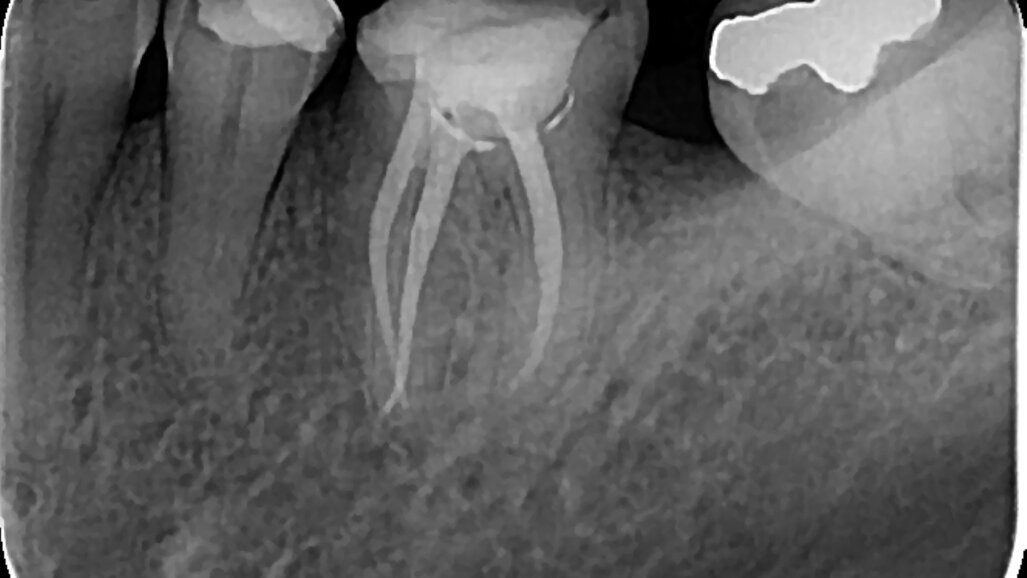

Slika 4. F One, single file sistem za kontinuiranu roraciju (Fanta Dental, Shanghai, China)

Ako sumiramo, recipročan pokret nam donosi sigurnu preparaciju uz blag apikalni pritisak pri čemu se imitira pokret balansiranih sila. Može se izvući zaključak da je zbog smanjenog cikličnog zamora i torzionog stresa produžen vek trajanja instrumenata (mada su jasna uputstva proizvođača o broju korišćenja). Potreban je jedan instrument za celokupnu obradu kanala (Slika 3), pa je vreme preparacije kraće, a primena jednostavna. Ipak, u slučaju kompleksne kanalne anatomije, često nismo u mogućnosti da jednim instrumentom završimo celokupnu preparaciju kanala. Sistemi koji koriste pokret kontinuirane rotacije 360 ° su pak mnogo brojniji i raznovrsniji na tržištu. Zbog većeg broja sekvenci, i vreme preparacije je duže, pa se godinama radilo na smanjenju broja instrumenata. Danas imamo dostupne sisteme od jednog instrumenta i za pokret kontinuirane rotacije, koji su izuzetno efikasni (Slika 4). Pokretom kontinuirane rotacije se postiže bolje uklanjanje debrija i manja je mogućnost za nastanak mikropukotina u dentinu. Problem cikličnog zamora i stresa je rešen kontrolom obrtnog momenta. Najvažnije, efikasnost rotirajućih instrumenata koji se aktiviraju ražličitim pokretima je ista. Na sreću, danas se sve više proizvođača odlučuje za endo motore koji nam nude mogućnost izbora, jer podržavaju obe kretnje. Na nama je da se u zavisnosti od postavljene dijagnoze, kompleksnosti kanalnog sistema, a prevashodno našeg znanja i iskustva opredelimo za određeni sistem i način aktivacije.